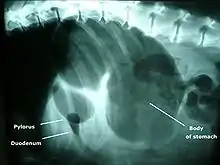

A diagnosis of GDV is made by several factors. The breed and history often gives a significant suspicion of the condition, and a physical examination often reveals the telltale sign of a distended abdomen with abdominal tympany. Shock is diagnosed by the presence of pale mucous membranes with poor capillary refill, increased heart rate, and poor pulse quality. Radiographs (X-rays), usually taken after decompression of the stomach if the dog is unstable, shows a stomach distended with gas. The pylorus, which normally is ventral and to the right of the body of the stomach, is cranial to the body of the stomach and left of the midline, often separated on the X-ray by soft tissue and giving the appearance of a separate gas-filled pocket (double-bubble sign).[4]